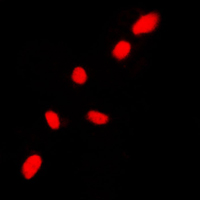

Immunofluorescent analysis of CHK2 staining in HL60 cells. Formalin-fixed cells were permeabilized with 0.1% Triton X-100 in TBS for 5-10 minutes and blocked with 3% BSA-PBS for 30 minutes at room temperature. Cells were probed with the primary antibody in 3% BSA-PBS and incubated overnight at 4 °C in a humidified chamber. Cells were washed with PBST and incubated with a DyLight 594-conjugated secondary antibody (red) in PBS at room temperature in the dark.